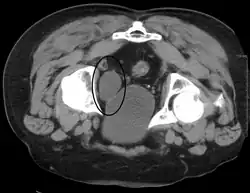

Investigation

A diverticulum of the bladder

A number of investigations are used to examine the bladder. The investigations that are ordered will depend on the taking of a medical history and an examination. The examination may involve a medical practitioner feeling in the suprapubic area for tenderness or fullness that might indicate an inflamed or full bladder. Blood tests may be ordered that may indicate inflammation; for example a full blood count may demonstrate elevated white blood cells, or a C-reactive protein may be elevated in an infection.

Some forms of medical imaging exist to visualise the bladder. A bladder ultrasound may be conducted to view how much urine is within the bladder, indicating urinary retention. A urinary tract ultrasound, conducted by a more trained operator, may be conducted to view whether there are stones, tumours or sites of obstruction within the bladder and urinary tract. A CT scan may also be ordered.

A flexible internal camera, called a cystoscope, can be inserted to view the internal appearance of the bladder and take a biopsy if required.